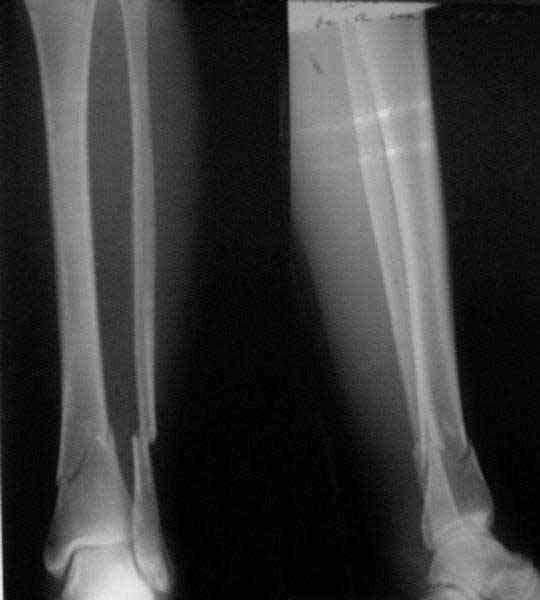

A typical case is attached, also an image with intra-op reduction obtained by a small wire distractor, in the moment of insertion a Poller wire in AP direction. Fixation by a SIGN nail. Despite the fibula was not fixed healing was obtained with the unchanged alignment.

Very interesting application, but is the final position in a little distal varus with some fibula

distraction? Would that have been eliminated by fibula plating?

At least both the ankle mortise and tibial alignment look acceptable, don't they?